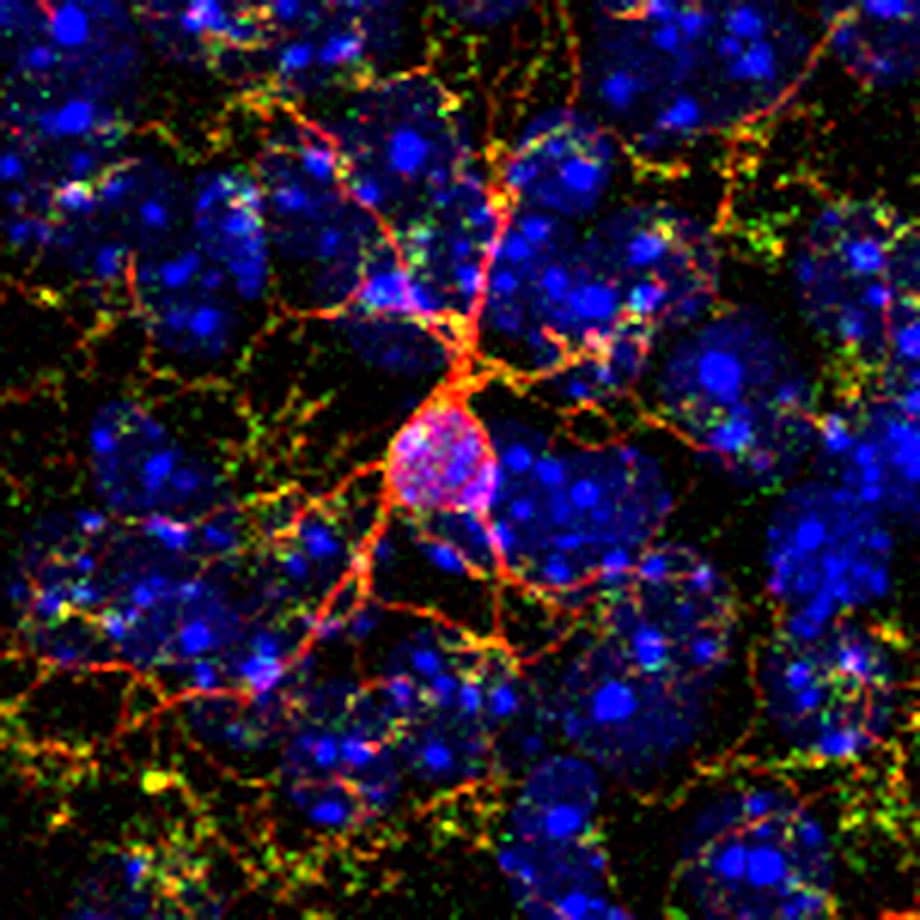

Descubren Mecanismo Que Reduce Los Efectos De La Cocaína En El Cerebro Exploramos el daño de la cocaína en el cerebro: efectos neurotóxicos, alteraciones en neurotransmisores y riesgos para la salud mental. Conclusión la cocaína es una droga altamente adictiva que afecta el cerebro de manera significativa. esto se debe a que la cocaína afecta los neurotransmisores en el cerebro, lo que provoca una sensación de placer y estimulación. La cocaína es una droga que ha causado preocupación a nivel mundial debido a su impacto en la salud de quienes la consumen. ¿sabías que tiene efectos devastadores en el cerebro? en este artículo, te explicaremos cómo la cocaína afecta al cerebro y cuáles son sus consecuencias a corto y largo plazo. El consumo de drogas trae consecuencias extremadamente negativas para todo el organismo, pero especialmente para el más importante, que es el cerebro. este y el corazón son los primeros órganos.

Cocaína Afecta La Zona Del Cerebro Que Recuerda Los Riesgos